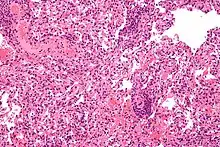

Lung transplant rejection

Deontological issues are issues about whether a person has an ethical duty or responsibility to take an action. Nearly all scholars and societies around the world agree that voluntarily donating organs to sick people is ethically permissible. Although nearly all scholars encourage organ donation, fewer scholars believe that all people are ethically required to donate their organs after death. Similarly, nearly all religions support voluntary organ donation as a charitable act of great benefit to the community. Certain small faiths such as Jehovah Witnesses and Shinto are opposed to organ donation based upon religious teachings; for Jehovah Witnesses this opposition is absolute whereas there exists increasing flexibility amongst Shinto scholars. The Roma People, are also often opposed to organ donation based on prevailing spiritual beliefs and not religious views per se.[142] Issues surrounding patient autonomy, living wills, and guardianship make it nearly impossible for involuntary organ donation to occur.